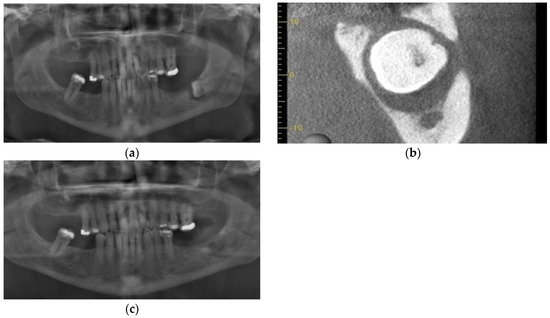

3.3. Case 3